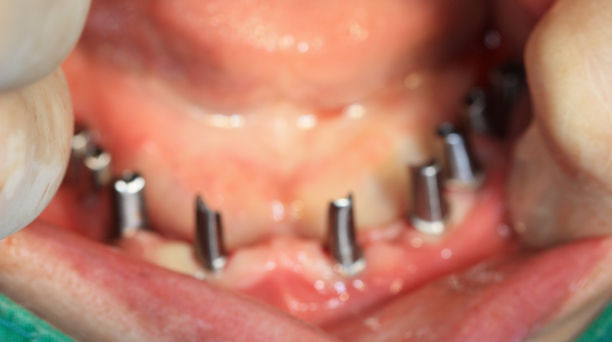

임플란트 식립 (전)

임플란트 식립 (후)